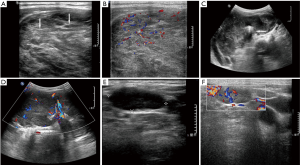

The dominant sonographic findings of PTL were large (average 4.8±1.7 cm, range 1.6–8.7 cm), solid (100%), ill-defined (81.5%) mass with echogenic strands (92.6%), posterior echo enhancement (85.2%) and without calcification (100%) (Table 2), while the dominant sonographic findings of ATC were large (average 5.8±2.1 cm, range 2.5–11.0 cm), solid (100%), ill-defined (100%) mass with macrocalcification or microcalcification (80%) (Table 2). PTL cases presented with diffuse type (25.9%) (Figure 1), nodular type (48.2%) (Figure 2) and mixed type (25.9%) (Figure 3). All ATC cases presented with nodular type (100%) (Figures 4,5). There is no significant difference in thyroid size, nodular size, margin, shape, echo texture, cystic change and vascularity on sonography between ATC and PTL groups (Table 2).

With regard to tumor-spreading patterns, in 15 patients with ATC, 13 patients had extra-thyroid extension into the surrounding soft tissue (Figure 4A), 1 patients invaded trachea, and 2 patients invaded jugular vein. In 27 patients with PTL, 14 patients had extra-thyroid extension into the surrounding soft tissue (Figures 2A,B,3B), 1 patients invaded trachea (Figure 1C).

A total of 25.9% (7/27) of PTLs presented with diffuse type, occupying entire thyroid without normal gland or most of the thyroid gland. Similar to the findings of the previous studies (20,26), all PTLs in our study are of B-cell lymphoma and predominantly of diffuse large-cell type, and the second most common histological type is MALT lymphoma. Most DLBCLs in our study showed nodular type (10/15, 66.7%). Compared to PTLs, all ATC cases were nodular type and limited to one lobe of thyroid, suggesting that PTL showed a propensity for more extensive disease at initial diagnosis. Plenty of ATC and PTL in our study showed direct invasion to the surrounding structures. Relevant literatures revealed that patients with ATC present with extensive local invasion at initial disease presentation in 15% to 50% of patients (27,28), and some research reported that invasion to the surrounding structures is rare in PTL (29,30). However, a few studies also reported PTL with aggressive appearance (31,32). Thus, the ultrasonographic features of local invasion were not specific enough to differentiate ATC from PTL.